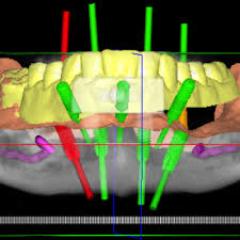

Chirurgia guidata

Attraverso la chirurgia guidata vengono realizzati impianti e forature chirurgiche in modo digitale ottenendo risultati altamente accurati, sicuri e prevedibili, direttamente il laboratorio.